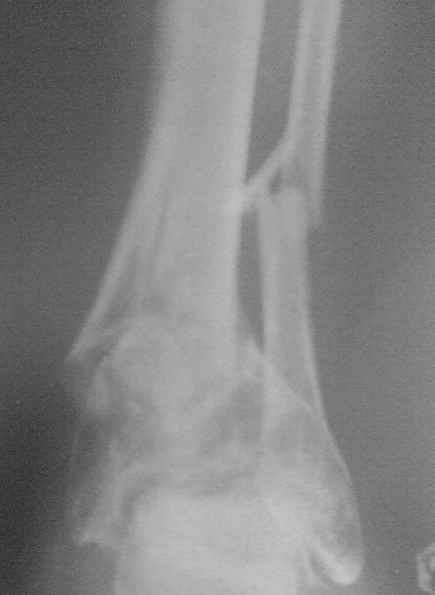

Уважаемые коллеги! В данном случае пациенту был наложен аппарат Илизарова, который через три месяца был снят из-за нагноения мягких тканей вокруг спиц.Ранняя нагрузка привела к смещению.

Благодарю за отзывы! Есть мнение, что в этой ситуации было бы резонно дать отсрочку на 1-2 месяца, т.к. остеопороз дистального отломка довольно выраженный и отек не меньше. После этого пойти открыто: остеотомия и накостный остеосинтез. А воспалительный процесс купирован.

Маловато информации, только один снимок в прямой проекции, не пойму есть сращение или нет???